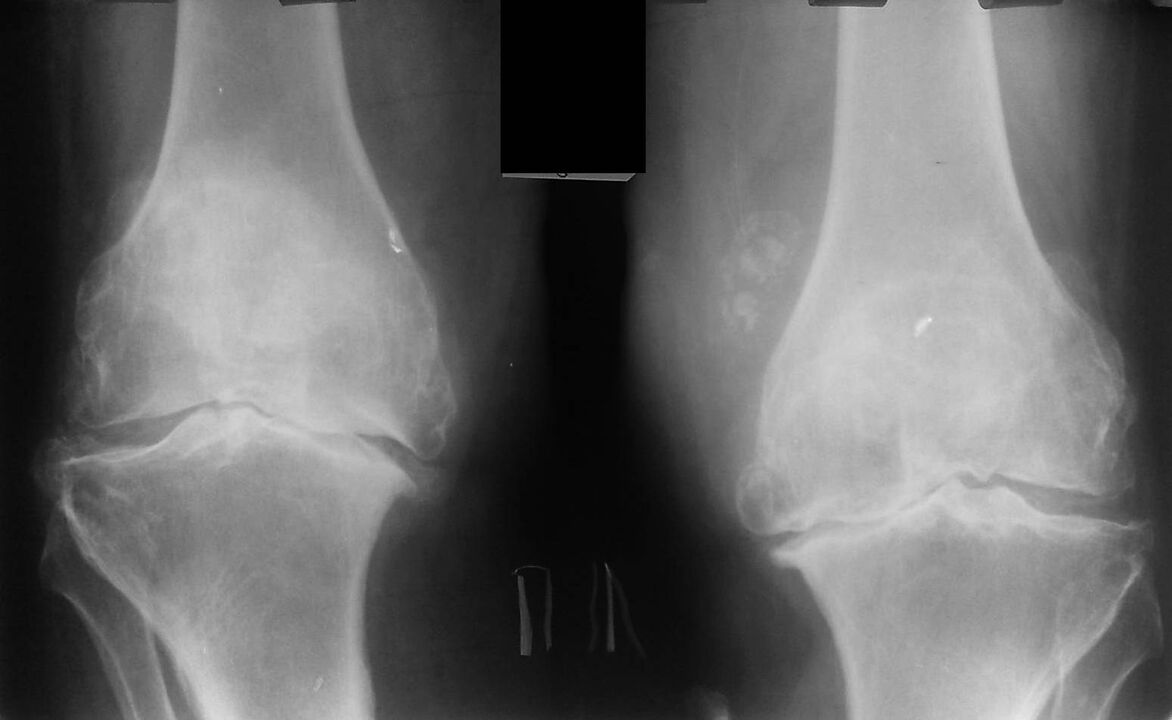

X-ray is a standard research method that allows you to confirm the diagnosis, determine the degree of pathological changes, monitor the dynamics of the process, and also allows you to exclude other pathological processes (eg tumors) in the tibia and femur.

It should be noted that the primary changes in the structures of the knee joint on X-rays may be missing. Subsequently, narrowing of the joint space and thickening of the subchondral area is determined. The articular ends of the femur and especially the tibia expand, the edges of the condyles become pointed.

- The second stage is characterized by more acute pain that does not stop with the immobility of the limb. A crunch appears. Fluid builds up in the joint cavity, and an X-ray shows the deformation and growth of the bone. At this stage, the patient tries in every possible way not to move the affected limb. The doctor prescribes injections and chondroprotectors - drugs that help restore cartilage tissue.

- In the last third stage, the pain becomes permanent and often worsens with changing weather conditions. The X-ray shows a significant deformity of the knee, which can be corrected only with surgery, the patient must take a complex of chondroprotectors. The patient's gait changes: he walks on half-bent legs or rolls from one side to the other.